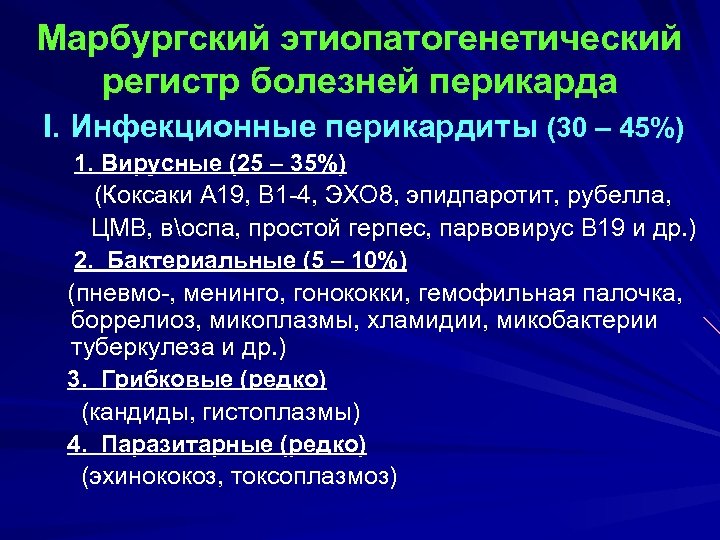

Марбургский этиопатогенетический регистр болезней перикарда I. Инфекционные перикардиты (30 – 45%) 1. Вирусные (25 – 35%) (Коксаки А 19, В 1 -4, ЭХО 8, эпидпаротит, рубелла, ЦМВ, воспа, простой герпес, парвовирус В 19 и др. ) 2. Бактериальные (5 – 10%) (пневмо-, менинго, гонококки, гемофильная палочка, боррелиоз, микоплазмы, хламидии, микобактерии туберкулеза и др. ) 3. Грибковые (редко) (кандиды, гистоплазмы) 4. Паразитарные (редко) (эхинококоз, токсоплазмоз)